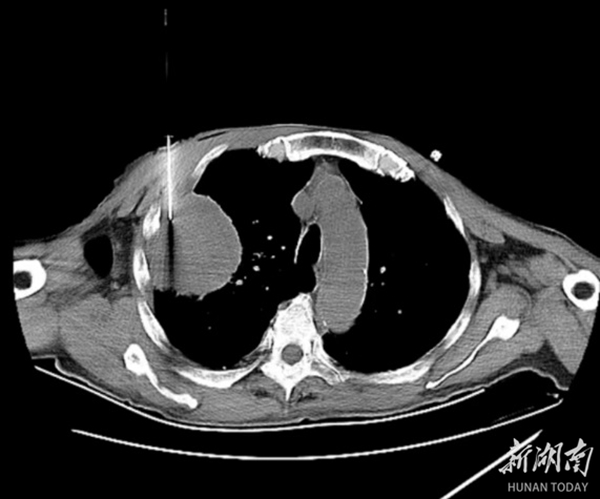

面对复杂的病情,呼吸与危重症医学科团队迅速行动,经过对肿块位置、大小及周围血供情况的全面评估,决定采用CT引导下经皮肺穿刺活检术。这一技术利用CT的高精度成像,引导穿刺针精准定位病灶,实现了安全、有效的组织取样。医患双方充分沟通与理解后,手术顺利进行,过程流畅,患者未感明显不适,且术后无并发症发生。

术后病理结果显示为肿瘤性病变,这一精准的诊断为患者后续的治疗提供了明确方向。CT引导下经皮肺穿刺活检术以其独特的优势,成为鉴别肺部肿块性质、明确组织类型的重要手段,针对有手术禁忌或患者拒绝手术的情况,更是展现了其重要性。